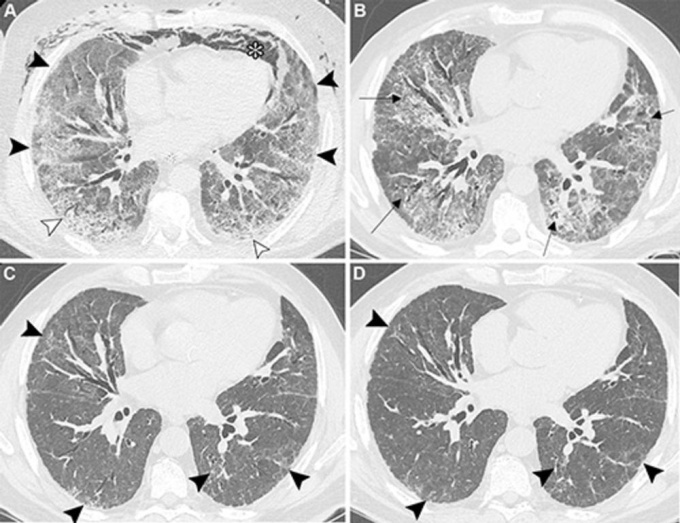

Radiologists face challenges distinguishing post–COVID residual lung abnormalities from interstitial lung disease (ILD) and ILA, which have different prognostic paths. Post–COVID changes tend to stabilize, while ILD and ILA can progress.